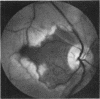

When axoplasmic transport in ganglion-cell axons is interrupted by ischaemia organelles accumulate in distended axon terminals at the edges of the infarct. This report illustrates the localized opaque swelling of nerve fibres shich develops at or near the optic disc after occlusion of the central retinal or posterior ciliary arteries. No such swelling occurs in patients who have a combined occlusion of these vessels.